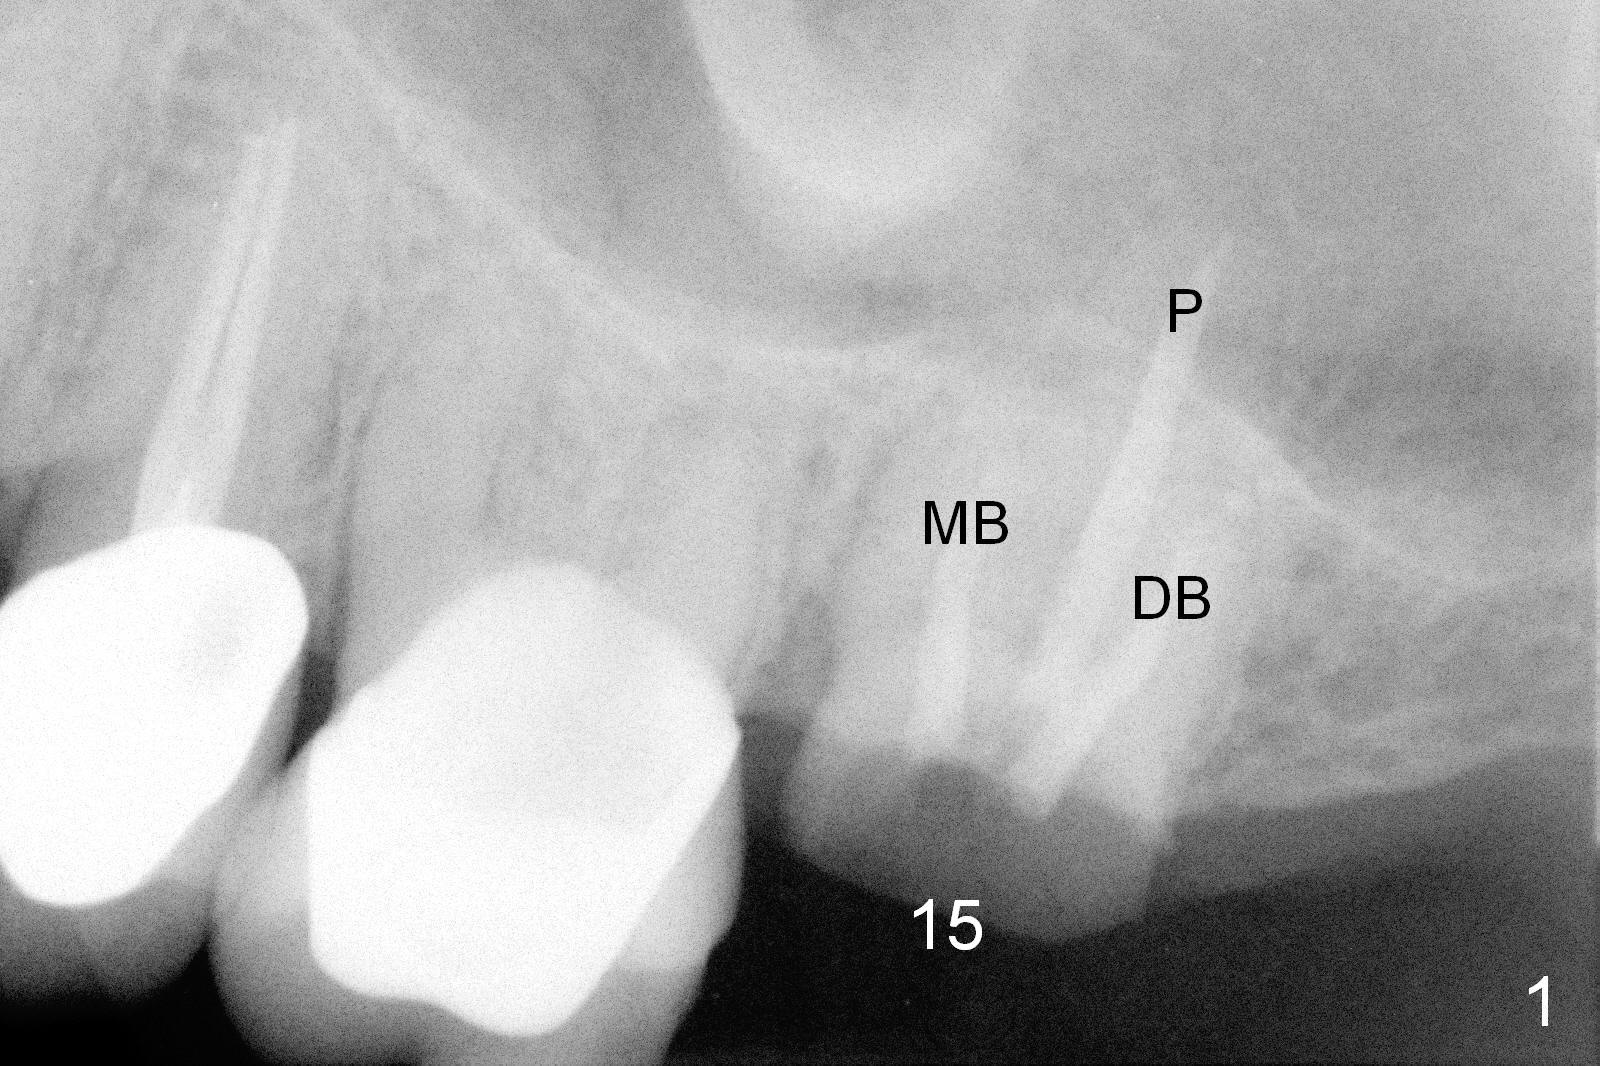

The tooth #15 of a 62-year-old man (CY) has been fractured for 4 years (Fig.1).  The 3 roots (MB, DB and P) appear to be approximated each other (Fig.1,3,4) so that when the tooth is extracted (using a surgical handpiece for sectioning), the socket should be single and large.  Treat the socket with Clindamycin.  If the socket proves to be flat on the top, the thickness of the sinus floor is approximately 2 mm.  If the bone is not so tough, use osteotomes to do sinus lift; otherwise use drills.  The depth of osteotomy should be tightly monitored.

PA shows that the depth of the osteotomy is approximately 17 mm (Fig.2), whereas CT 14 mm (Fig.3,4).  Intraop measurement will determine the depth.